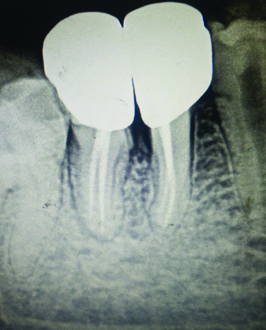

A 34-year-old male patient presented to the Department of Conservative Dentistry and Endodontics with a complaint of persistent low grade pain in right mandibular first molar since a fortnight. There was no contributory medical history or history of other dental treatment. Intraoral examination revealed caries with 45 and 46. No other teeth in the oral cavity were cariously involved, 46 showed deep mesio-occlusal caries involving the pulp and was sensitive to vertical percussion with no mobility or periodontal involvement. Vitality testing with the electric pulp tester gave a delayed response indicating irreversible pulpitis. Root canal treatment was initiated and after pulp extirpation, a rough working length estimation X-ray was taken. On this radiographic examination, an incomplete vertical fracture line involving the furcation area was noted [Table/Fig-1]. The bone support of both roots was good and not periodontally compromised in any manner. There was no periodontal or furcation involvement seen in relation to 46. A disto-occlusal composite resin restoration was planned for 45. An assessment of all findings was made and a treatment protocol was developed to achieve functional preservation of the tooth in the arch.

Diagnostic radiograph of 46 showing incomplete vertical fracture in the furcation area.

In the treated case, the fracture line, observed in the initial radiograph [Table/Fig-1], extended from the furcation area towards the point of bifurcation at the floor of the pulp chamber. During access cavity preparation, it was observed that the fracture line did not extend into the pulp chamber; thus, confirming the diagnosis of incomplete vertical furcation fracture. Vertical furcation fracture is a vertical crack that extends vertically from the floor of the pulp chamber in a mandibular molar towards the furcation area of the roots. The pulp is mostly involved in a vertical furcation crack and the tooth is vaguely symptomatic until the fracture line propagates and mobility sets in. The tooth rarely separates into two pieces because the tooth is held in position by the surrounding bone. The prognosis for this type of crack is fair but it depends on how deep the crack extends into the internal aspect of the tooth. The options are to treat the tooth with a root canal followed by a build up, post and crown or to extract the tooth [3]. Several classifications have been proposed to better explain vertical tooth fractures [4,5] (by Leubke and others), but there is scant mention in literature of vertical fractures restricted to the furcation area with incomplete progression of the fracture line.